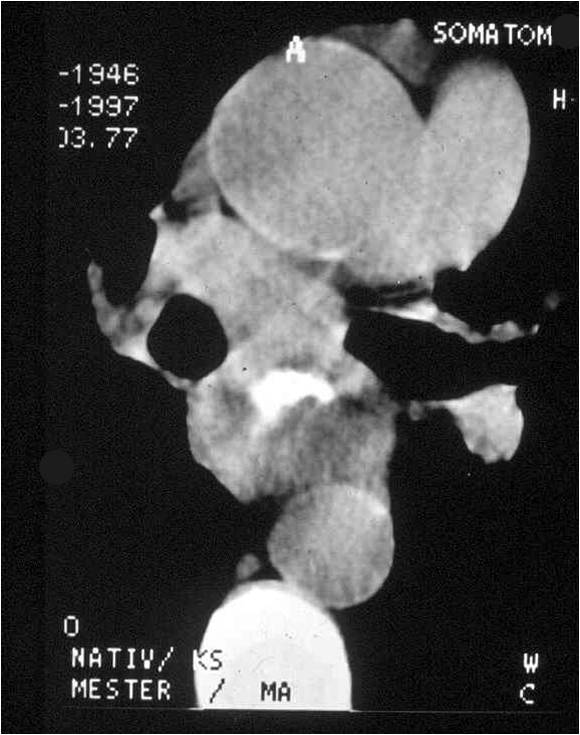

Image

Fig.7.: The CT scan shows prominent wall thickening in the narrowed esophageal segment.